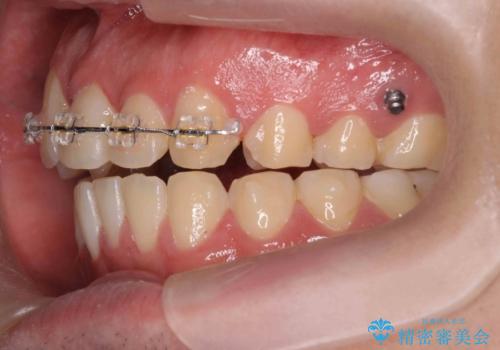

- 矯正装置

- ワイヤー矯正 → インビザライン

- 前歯の見た目に悩まれて来院されました。

当初他院では、抜歯を行いセラミックブリッジを提案されていましたが、他の方法はないかと総合歯科治療を行う当院へと相談来院されました。

「時間がかかっても良いので、できれば歯を抜かずに矯正治療で治したい。」という強い希望があったので、矯正治療で歯並び・審美性の改善を計画します。